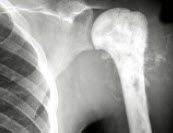

27、单项选择题

男,28岁,右肱骨上段肿痛1月,疼痛以夜间明显,如图所示,最可能的诊断是()

A.溶骨性骨肉瘤